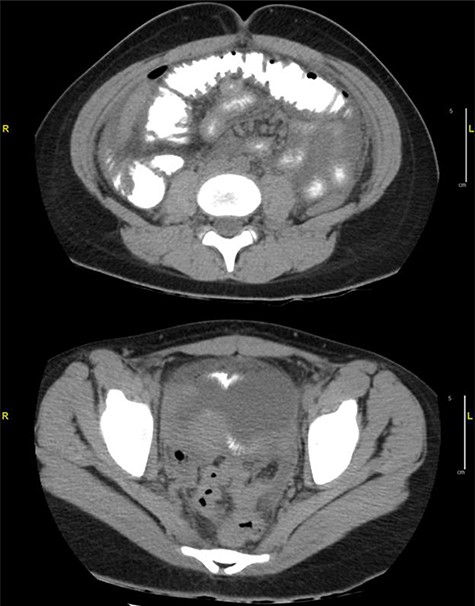

Case 2: A 13-year-old girl presented to the ED with a 3-day history of severe diffuse intermittent abdominal pain, worse in the periumbilical area, associated with nausea, vomiting and non-bloody diarrhea. No significant history was reported. On exam, the patient appeared sick, in acute distress, tachycardic and tachypneic with abdominal exam revealing diffuse tenderness with peritoneal signs. Laboratories showed normal WBC but lactic acidosis. Chest X-ray did not show free air under diaphragm (Fig. 3) and abdominal ultrasound showed moderate fluid in right upper quadrant of abdomen, for which CT of the abdomen and pelvis was ordered and it revealed free mesenteric fluid and extraluminal air in the pelvis suspicious for hollow viscus perforation (Fig. 4).

Diffuse infiltration of the mesentery is seen. A component of bowel wall thickening is seen in the distal ileum and the transverse colon. In the pelvis, a focus of extraluminal air is seen on the right. Free mesenteric fluid is seen as well.